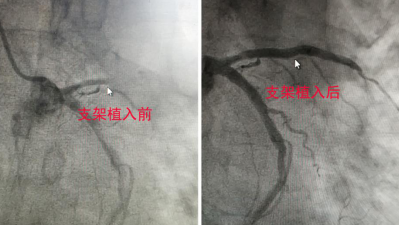

前降支近端完全闭塞,右冠状动脉近段次全闭塞……造影剂显示,李师傅心脏的3条重要大血管均有不同程度的堵塞情况。“最严重的当属前降支近端完全闭塞,前降支作为冠脉重要的一根血管,负责心脏50%左右的供血,近端完全闭塞的前降支会引发心脏供血不足,导致心脏衰竭、猝死等。”我院综合内科一(心内科)主任张青卿说。

开通血管刻不容缓!我院张瑶俊博士心血管工作室专家张瑶俊教授带领介入团队迅速为患者开通堵塞的“心路”。

前降支近端血管的闭塞,相当于看不见路的方向,这给手术带来很大的困难和风险,不仅仅只是操作难度的成倍增加,因为一旦走错了“路”,就可能造成血肿、夹层,甚至血管破裂,危及患者生命。张瑶俊教凭借对冠脉解剖的熟悉,准确地植入心脏支架,血流随即恢复了畅通。李师傅胸闷、胸痛的症状得到了很大改善。